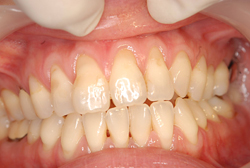

症例1【50代女性】主訴・前歯4本の根が見えるのが気になる。根面被覆(Root coverage)口蓋(上顎)から歯肉を採取し、露出している根面に歯肉を移植し被覆。

治療前

主訴 上顎前歯4本の根が見えるのが気になる。

根面被覆(Root coverage)口蓋(上顎)から歯肉を採取し、露出している根面に歯肉を移植し被覆。

露出が目立たなくなり、歯肉のラインもきれいに改善された。

費用 10万(歯肉移植術)